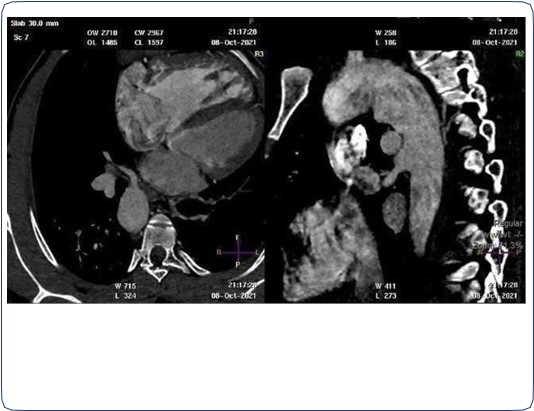

Two arterial supplies to the right lung arising from the descending aorta. A dominant one arising from the medial side that supplies the right upper lobe (Figure 3). Another smaller branch supplies the right middle and lower lobes (Figure 4).

Small blind-ended artery arising from the aortic arch at the take-off point of the left brachiocephalic artery (Figure 5) with non-visualization of left main pulmonary artery (Figure 3A). Multiple small arterial collaterals at the left hilum supplying the relatively hypo-plastic left lung (Figure 3A).

Figure 3: Contrast-enhanced CT chest axial (A), sagittal and coronal (B) views, showing an arterial supply to the right upper lobe arising from the descending aorta. Also there is an absent left pulmonary artery with multiple small collaterals at the left hilar region. Relative hypo-plastic left lung.